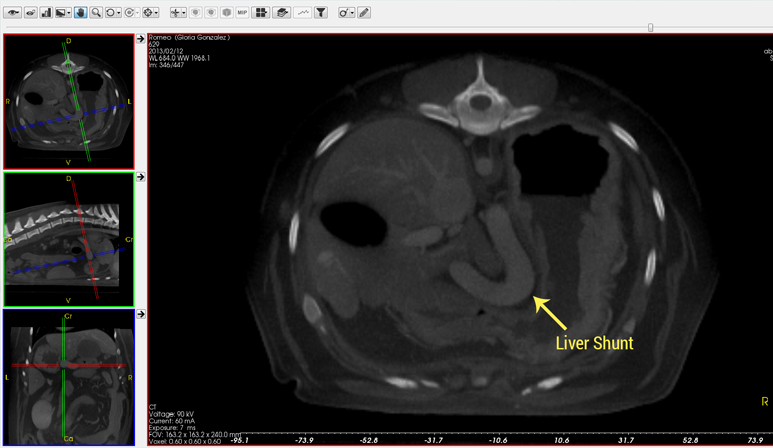

CT scans, also called computed tomography, give veterinarians a detailed look inside your pet's body. This technology captures cross-sectional images, allowing for precise diagnoses that traditional X-rays or ultrasounds might miss.

Once your pet is comfortably anesthetized, our technician gently positions them on the scanner table. Using state-of-the-art veterinary CT technology, our team captures hundreds of detailed internal images in minutes. We meticulously scan the area indicated by your veterinarian, making sure no detail is missed.

CT scans are one of the most advanced diagnostic tools in modern veterinary medicine. They help uncover the root cause of issues that may not show up with standard X-rays or bloodwork.

CT scans help diagnose a wide variety of conditions, including fractures, cancer, brain and spinal issues, nasal disease, and internal injuries. They are especially helpful for complex cases where standard diagnostics have not provided clear answers.